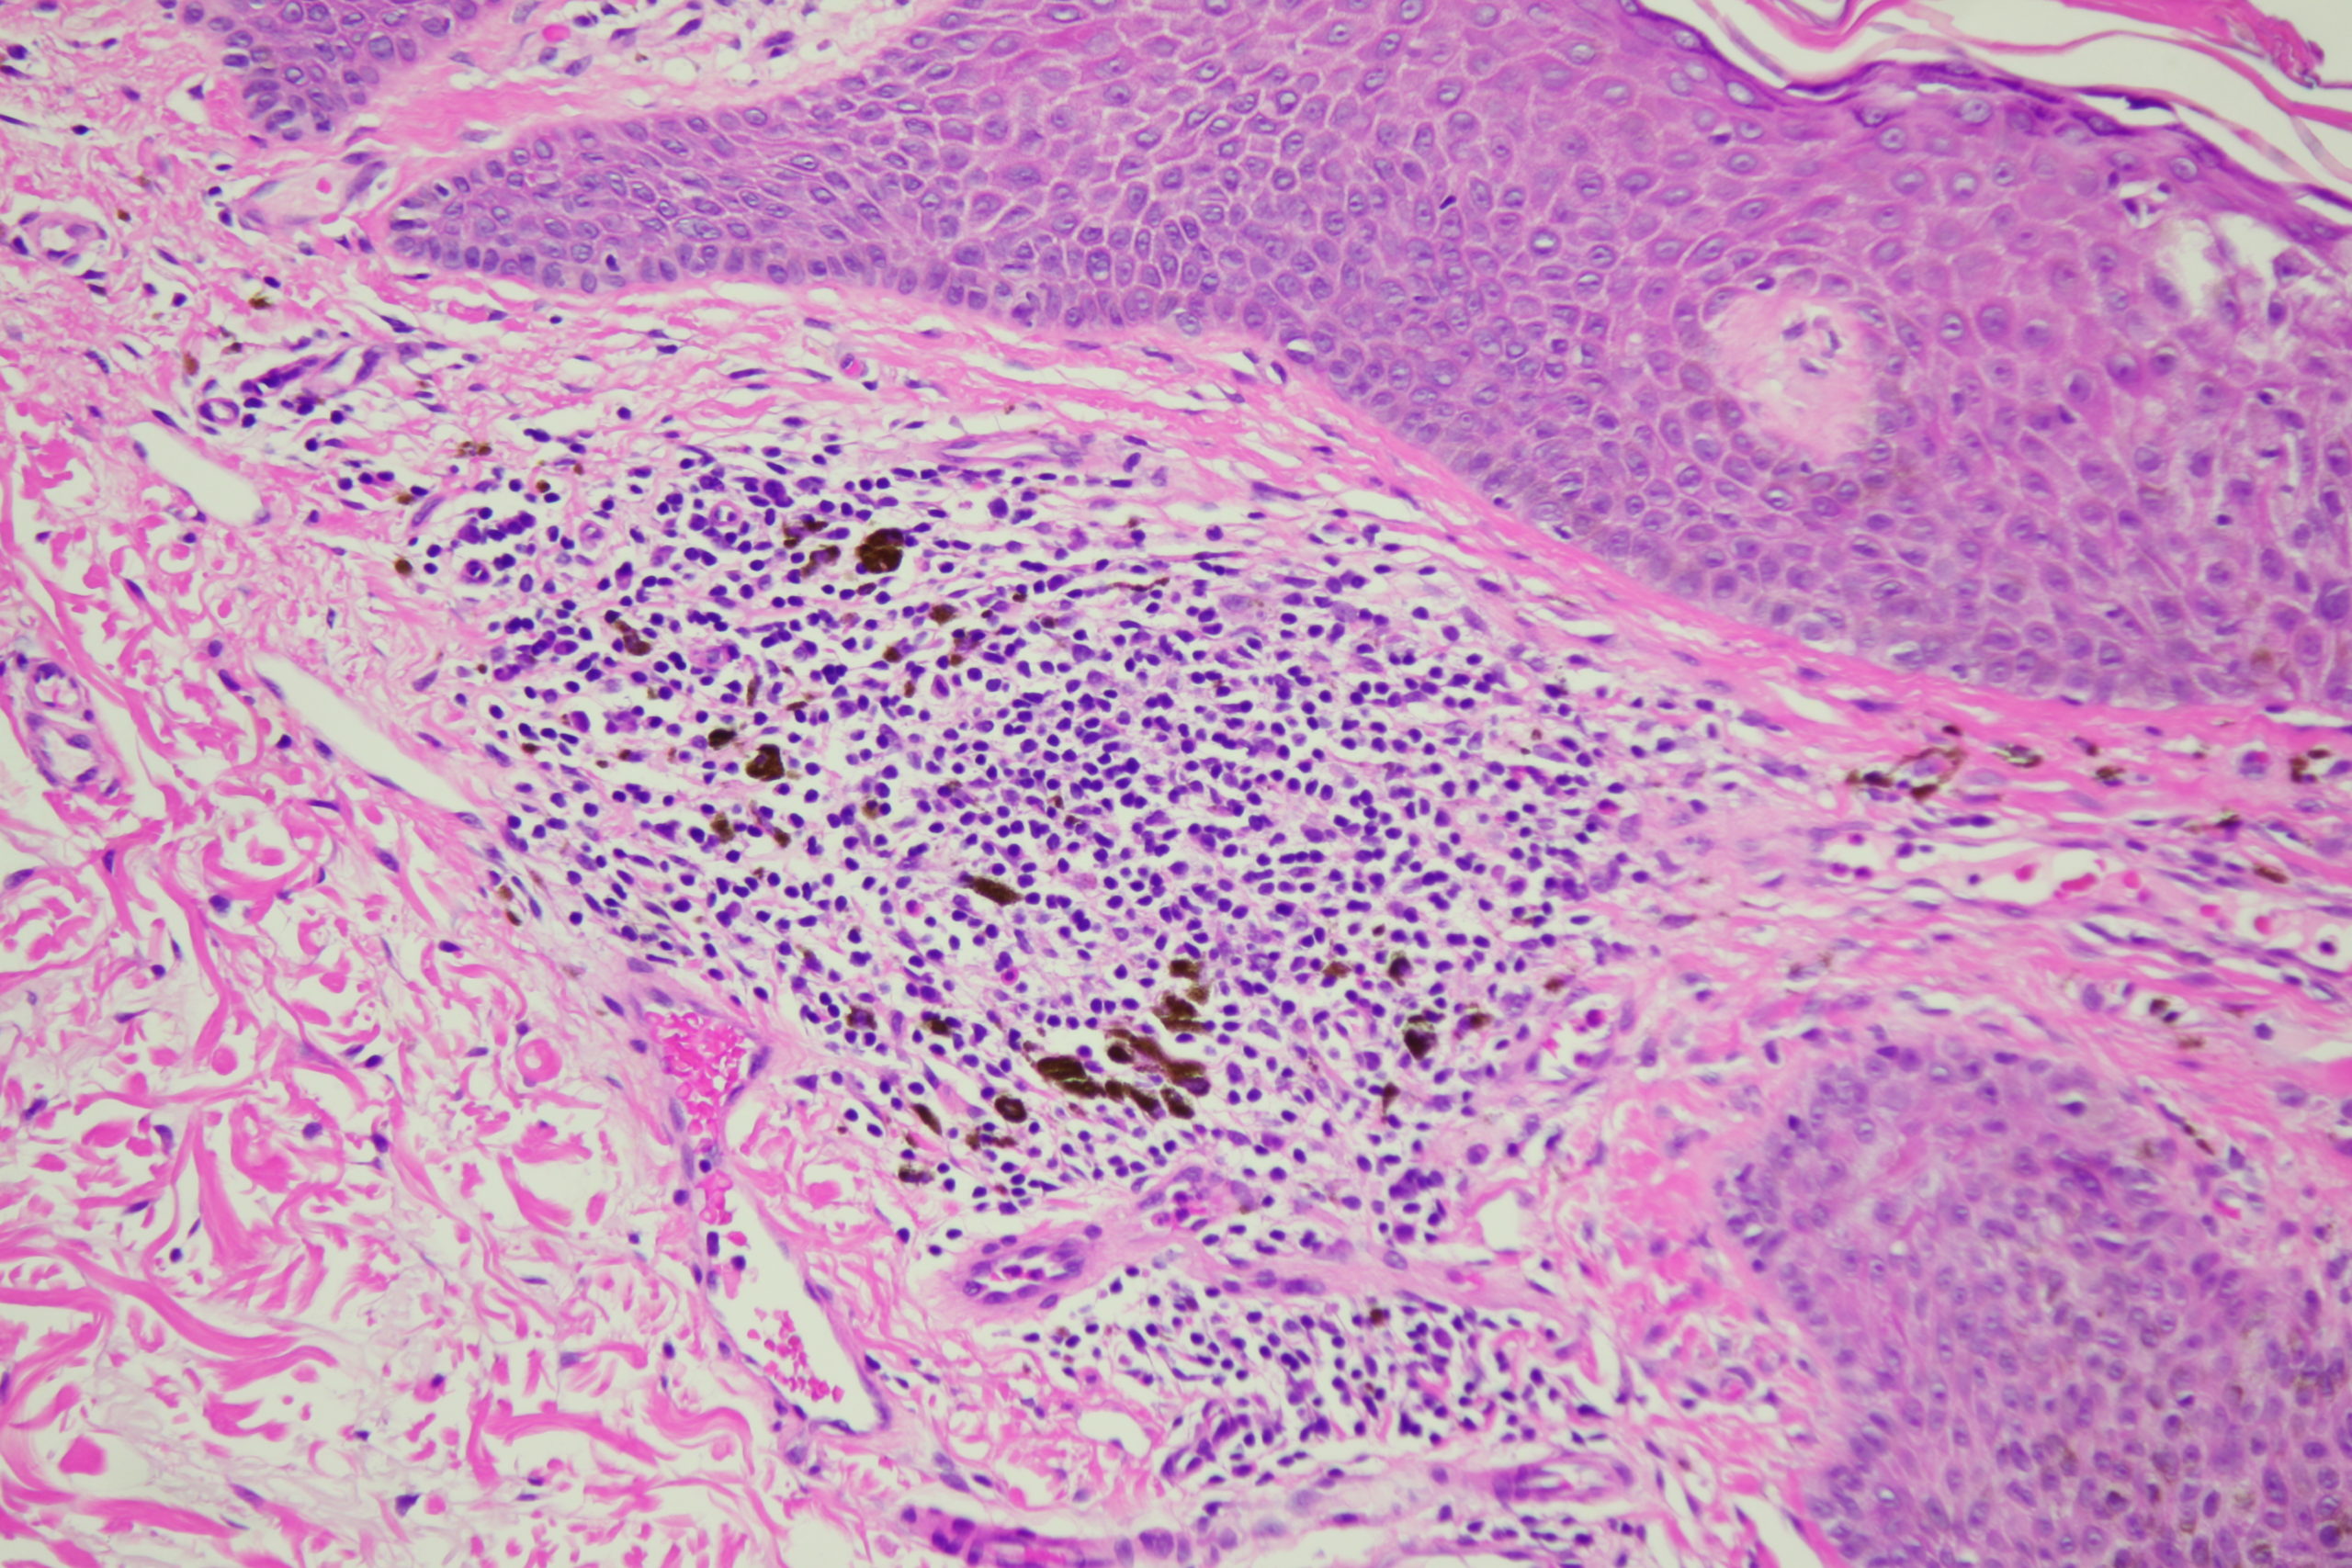

Image Number #3795 (Seborrhoeic keratosis irritated)

Diagnosis: Seborrhoeic keratosis irritated

Description: Dark blue blackish structureless areas surrounding paler center and white surface scales Broad coarse fatty brownish radial circumferential structures and black dots

A man in his 70s with this pigmented lesion on his upper back noted during a skin check.I look carefully at all dark seb k like lesions because lentigo maligna can easily involve a seb k. However I am always concerned about missing a seb k like melanoma. What do you think of this one? Note the pink colour surrounding it.